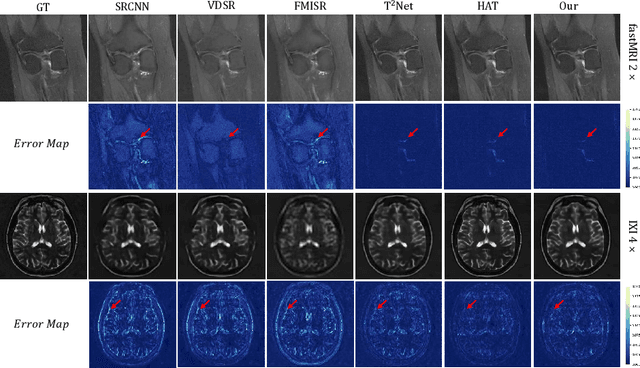

Abstract:High-resolution medical images can provide more detailed information for better diagnosis. Conventional medical image super-resolution relies on a single task which first performs the extraction of the features and then upscaling based on the features. The features extracted may not be complete for super-resolution. Recent multi-task learning,including reconstruction and super-resolution, is a good solution to obtain additional relevant information. The interaction between the two tasks is often insufficient, which still leads to incomplete and less relevant deep features. To address above limitations, we propose an iterative collaboration network (ICONet) to improve communications between tasks by progressively incorporating reconstruction prior to the super-resolution learning procedure in an iterative collaboration way. It consists of a reconstruction branch, a super-resolution branch, and a SR-Rec fusion module. The reconstruction branch generates the artifact-free image as prior, which is followed by a super-resolution branch for prior knowledge-guided super-resolution. Unlike the widely-used convolutional neural networks for extracting local features and Transformers with quadratic computational complexity for modeling long-range dependencies, we develop a new residual spatial-channel feature learning (RSCFL) module of two branches to efficiently establish feature relationships in spatial and channel dimensions. Moreover, the designed SR-Rec fusion module fuses the reconstruction prior and super-resolution features with each other in an adaptive manner. Our ICONet is built with multi-stage models to iteratively upscale the low-resolution images using steps of 2x and simultaneously interact between two branches in multi-stage supervisions.

Abstract:In this paper, we propose a self-prior guided Mamba-UNet network (SMamba-UNet) for medical image super-resolution. Existing methods are primarily based on convolutional neural networks (CNNs) or Transformers. CNNs-based methods fail to capture long-range dependencies, while Transformer-based approaches face heavy calculation challenges due to their quadratic computational complexity. Recently, State Space Models (SSMs) especially Mamba have emerged, capable of modeling long-range dependencies with linear computational complexity. Inspired by Mamba, our approach aims to learn the self-prior multi-scale contextual features under Mamba-UNet networks, which may help to super-resolve low-resolution medical images in an efficient way. Specifically, we obtain self-priors by perturbing the brightness inpainting of the input image during network training, which can learn detailed texture and brightness information that is beneficial for super-resolution. Furthermore, we combine Mamba with Unet network to mine global features at different levels. We also design an improved 2D-Selective-Scan (ISS2D) module to divide image features into different directional sequences to learn long-range dependencies in multiple directions, and adaptively fuse sequence information to enhance super-resolved feature representation. Both qualitative and quantitative experimental results demonstrate that our approach outperforms current state-of-the-art methods on two public medical datasets: the IXI and fastMRI.

Abstract:In this paper, we propose a new architecture, called Deform-Mamba, for MR image super-resolution. Unlike conventional CNN or Transformer-based super-resolution approaches which encounter challenges related to the local respective field or heavy computational cost, our approach aims to effectively explore the local and global information of images. Specifically, we develop a Deform-Mamba encoder which is composed of two branches, modulated deform block and vision Mamba block. We also design a multi-view context module in the bottleneck layer to explore the multi-view contextual content. Thanks to the extracted features of the encoder, which include content-adaptive local and efficient global information, the vision Mamba decoder finally generates high-quality MR images. Moreover, we introduce a contrastive edge loss to promote the reconstruction of edge and contrast related content. Quantitative and qualitative experimental results indicate that our approach on IXI and fastMRI datasets achieves competitive performance.